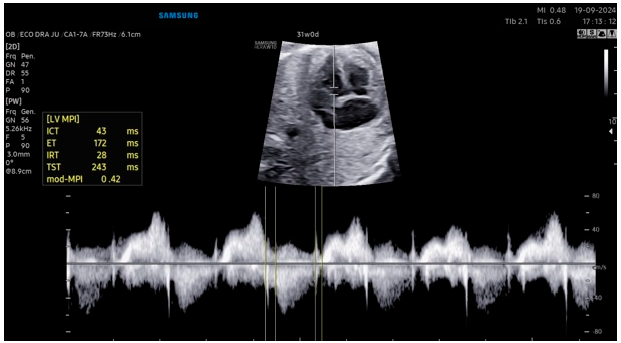

With technological advancements, automatic methods based on AI have been developed to optimize daily practice in Fetal Medicine by improving the accuracy and reproducibility of fetal cardiac measurements. The HeartAssist® technology (Samsung Healthcare, Gangwon-do, South Korea) operates by capturing detailed real-time ultrasound images of the fetal heart. Utilizing advanced algorithms, the system analyzes these images, identifying essential cardiac structures such as the ventricular chambers, interventricular septum, and cardiac valves. Based on these identifications, HeartAssist® automatically calculates crucial biometric measurements, such as the diameter of the aorta, the thickness of the interventricular septum (IVS), and the diameter of the left ventricle [3] (Fig. 1).

Figure 1: The images illustrate automated measurements of fetal heart parameters by HeartAssist®: (A) Width of the atria and ventricles in the four-chamber view; (B) Ascending aorta diameter in the left ventricular outflow tract view; (C) Diameter of the pulmonary artery in the right ventricular outflow tract view; (D) Diameter of the ductus arteriosus and aortic isthmus in the three vessels and trachea view.

Pietrolucci et al. [3] evaluated the agreement between visual and automatic methods in assessing the adequacy of fetal cardiac images obtained during second-trimester scans. Views of the left and right outflow tracts of the four-chamber, along with three vessels and the trachea view, were obtained from 120 consecutive low-risk singleton pregnancies undergoing second-trimester ultrasound between 19 and 23 weeks. For each view, quality assessment was performed by a specialist sonographer and by an AI software (HeartAssist®). Cohen’s κ coefficient was used to assess the agreement rates between the two techniques. The number and percentage of images deemed visually adequate by the specialist or with HeartAssist® were similar, with a percentage >87% for all considered cardiac views. The Cohen’s κ coefficient values were 0.827 (95% CI, 0.662–0.992) for the four-chamber view, 0.814 (95% CI, 0.638–0.990) for the left ventricle outflow tract, and 0.838 (95% CI, 0.683–0.992) for the three vessels and trachea, indicating good agreement between the two techniques. The authors concluded that HeartAssist® enabled automatic visualization of fetal cardiac structures, achieved the same accuracy as specialized visual assessment, and has the potential to be applied in evaluating the fetal heart during ultrasound screening for CHD in the second trimester of pregnancy.